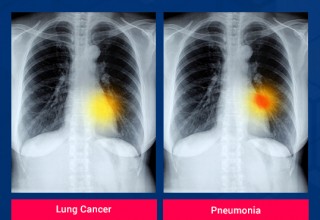

AI in Image Analytics

OSP is helping to reimagine the human vision with the real-time image analytics AI software with remarkable accuracy can enhance business efforts in industries like healthcare, retail, security, logistics and more.